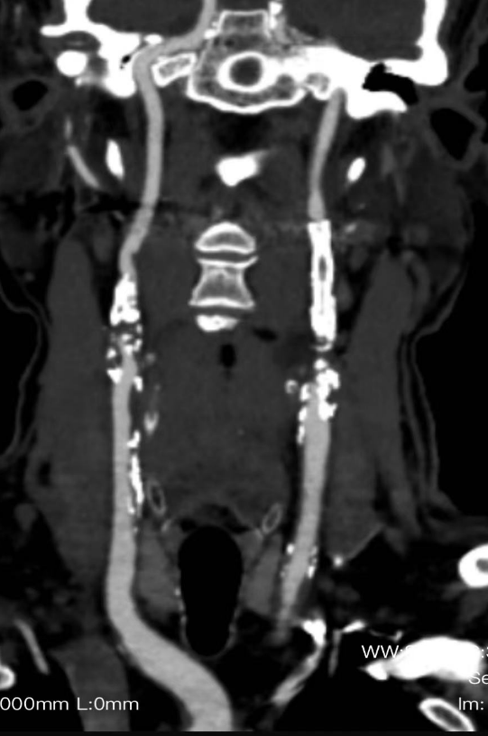

CASE 1:79岁男性,双侧颈动脉重度钙化狭窄,采用IVL预处理后置入支架,术后造影显示管腔通畅。

双侧颈动脉重度

钙化狭窄

IVL后管腔

获得良好

术后造影

显示管腔通畅